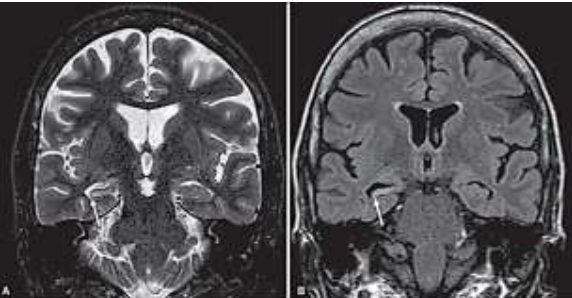

Paciente de 26 anos com epilepsia refratária ao tratamento medicamentoso, submetido à investigação complementar com ressonância magnética do crânio. No momento assintomático.

O provável diagnóstico para o caso é: